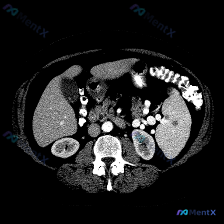

这是一次增强扫描(动脉晚期/门脉期),图像质量挺好:

- 脾脏:实质中部见一类圆形低密度影,边界尚清,周边未见明显强化(划重点)。

- 其他发现:右肾有个小的类圆形低密度影(考虑囊肿);腹主动脉有点状钙化,腰椎有增生硬化(符合老年性改变)。

- 排除项:肝脏、胰腺没看到明确占位;没有腹水,没有淋巴结肿大;肠壁也不厚。